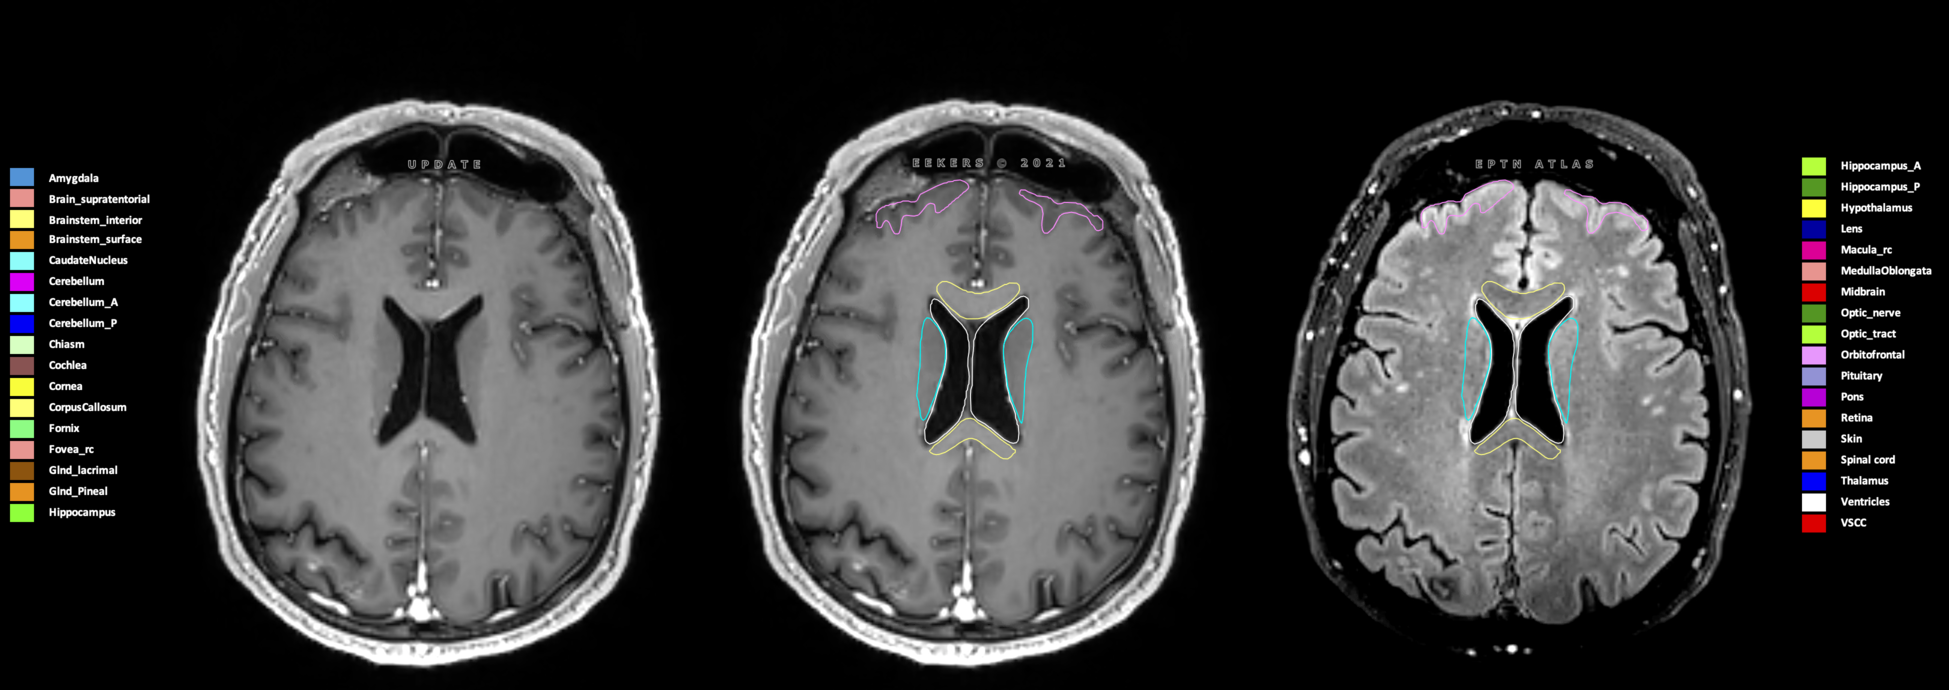

Eekers et al. have published an international neurological atlas for contouring of organs at risk in consensus with the European Particle Therapy Network (EPTN) in 2018 and an update in 2021. The purpose of this consensus atlas is to decrease inter- and intra-observer variability in delineating OARs relevant for neuro-oncology.

Included are all OARs known to be relevant for radiation-induced toxicity in neuro-oncology: brain, brainstem (midbrain, pons, medulla oblongata), chiasm, cerebellum (anterior & posterior), cochlea, cornea, hippocampus (anterior & posterior), hypothalamus, lens, lacrimal gland, optic nerve, pituitary, skin, and vestibular & semicircular canals. To further facilitate research on cognition, vision and radiological changes after irradiation of the brain, potential clinically-relevant OARs are included: amygdala, caudate nucleus, cerebellum (anterior & posterior), corpus callosum, fornix, macula, optic tract, orbitofrontal cortex, periventricular space (PVS), pineal gland, and thalamus.

Three-dimensional delineation of the 25 consensus OARs for neuro-oncology are shown on CT (WW/WL 120/40, 3000/600), 3T MR images, (T1Gd, T2FLAIR 1mm) and 7T MR (MP2RAGE 0.7 mm). All are presented in transversal, sagittal and coronal view.